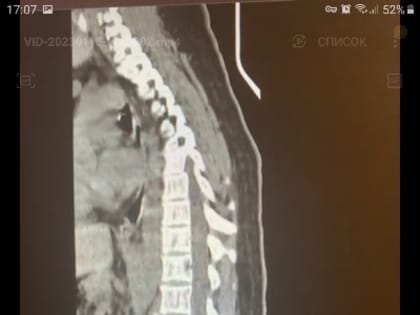

Клинический случай. Травма после катания на тюбинге.

Новый клинический случай у травматологов КМКБСМП. Молодая женщина была доставлена в больницу с травмой позвоночника, которую получила во время спуска с горы на тюбинге.

Красноярке после катания на «плюшке» пришлось винтами закреплять позвоночник

КРАСНОЯРСКИЙ КРАЙ, /НИА-КРАСНОЯРСК/. По словам медиков, порой спуски с горок заканчиваются инвалидностью.

Красноярка получила травму позвоночника во время катания на тюбинге

В Красноярске врачи БСМП прооперировали молодую женщину, которая получила серьезную травму позвоночника во время спуска с горы на тюбинге.